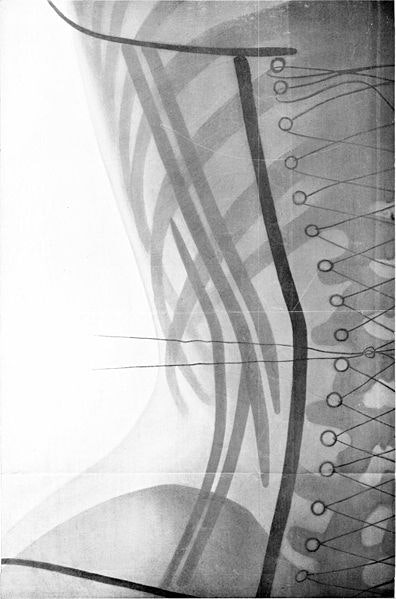

Pero miremos de nuevo a la época final de auge del corsé, antes de 1914. Aquí es donde entran en juego los rayos X que menciono en el título del post. El uso del corsé estaba tan extendido, y tantas veces se llevaba a extremos tan peligrosos, que un médico francés que atendía al nombre de Ludovic O’Followell, publicó todo un tratado médico acerca de esta prenda de vestir.

Su objetivo era el dar a conocer todos los detalles acerca de cómo se podía utilizar el corsé con fines médicos, estéticos pero, también, mostrar cómo podía llegar a modificar la morfología femenina y hasta la fisiología normal. Se ha dicho muchas veces que el trabajo con rayos X sobre mujeres con corsé que llevó a cabo Ludovic O’Followell estaba destinado a denunciar las patologías originadas por el mal uso de la prenda. A lo largo del tratado Le Corset, que contó con una edición en 1905 y una ampliación en 1908, se mencionan los peligros de ciertos usos del corsé, pero también se ensalza su empleo cuidadoso. Además, cabe recordar que este médico era columnista de la revista de moda Les Dessous Elegance. Las siguientes imágenes pertenecen a su tratado sobre el corsé y hablan por sí mismas.